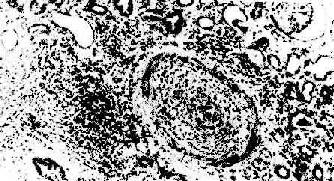

图4-4 肾移植急性排斥反应 肾间质水肿,肾小管上皮细胞变性,间质及毛细血管内有大量单核细胞 (2)血管型排斥反应:主要为抗体介导的排斥反应(CMC,ADCC和免疫复合物形成),往往在稍后出现,以突出的血管病变为特征。表现为肾细、小动脉的坏死性血管炎,可呈弥漫或局灶性分布。免疫荧光证实有免疫球蛋白、补体及纤维蛋白沉积,肾小球毛细血管袢亦可受累。纤维蛋白样坏死的血管壁内常有淋巴细胞、泡沫细胞及中性粒细胞浸润,腔内可有血小板凝集、血栓形成(图4-5)。后期的血管内膜纤维化,管腔狭窄。间质内常有不同程度淋巴细胞、巨噬细胞及浆细胞浸润。肉眼观,肾常明显肿大,呈暗红色并有出血点,有时可出现黄褐色的梗死灶,可伴有肾盂及肾盏出血(图4-6).临床上,移植肾出现功能减退,大剂量免疫抑制剂疗效不佳。

图4-5 肾移植急性排斥反应 小叶间动脉呈纤维素样坏死,并有大单核细胞及中性白细胞浸润和血栓形成